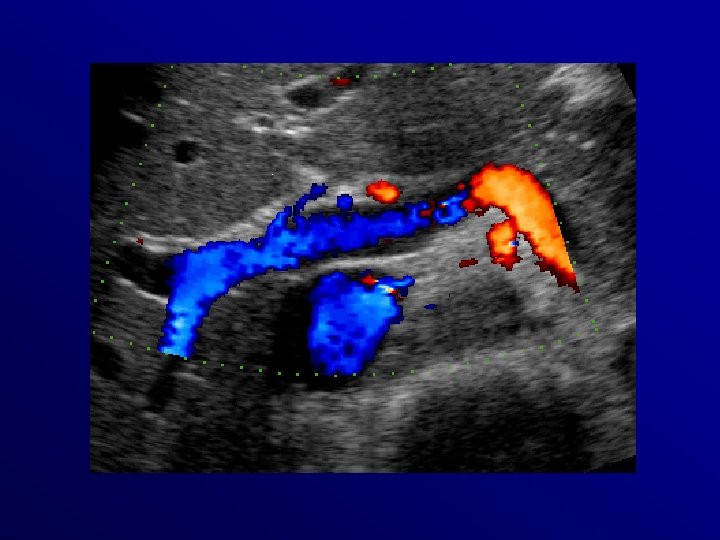

Trombosi completa splenoportale